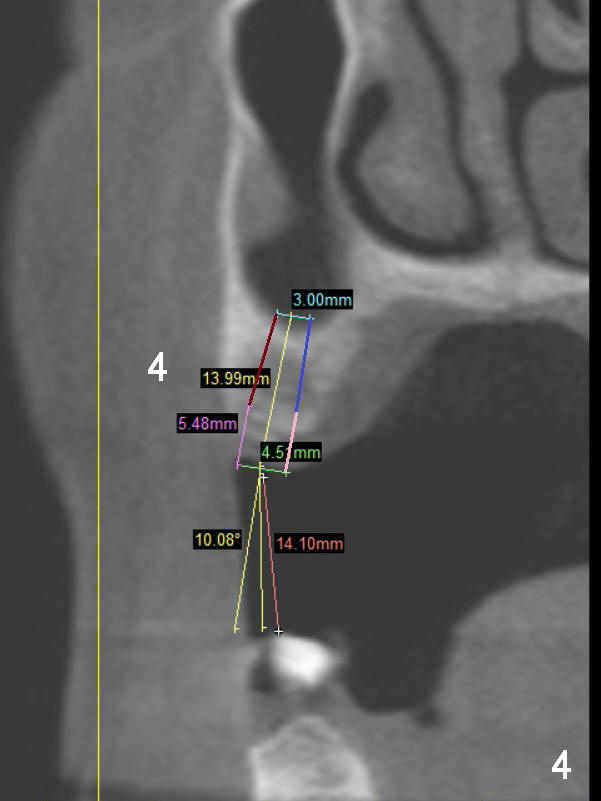

A 68-year-old lady has several missing teeth (Fig.1,2). She has agreed to have an implant at the site of #3 (Fig.3) to stabilize an upper removable partial denture (RPD). The latter will be more stable if an extra implant is placed at #6 (Fig.1,2,6). There is enough bone to place implants at #4,5 (Fig.4,5). Bone density at these sites is low. Osteotomy should be underprep with bone condensation. Edentulous space is high so long abutments are required (9 mm instead of 3 or 5 mm (regularly used)). Angled abutments should be prepared.